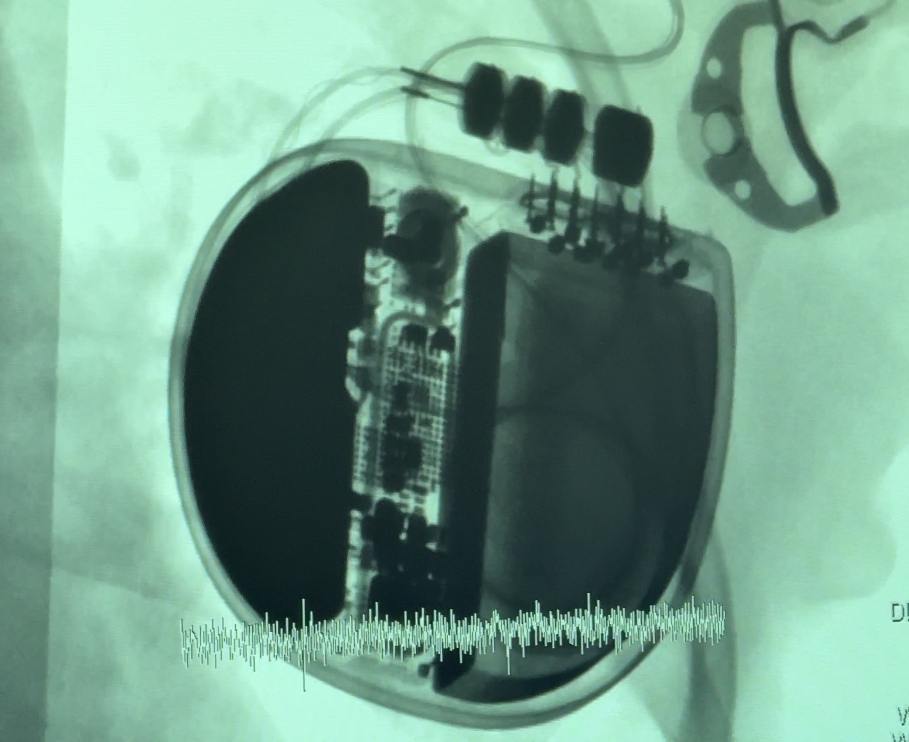

— Из-за небольшого возраста пациента удаление опухоли могло быть слишком рискованным, поэтому мы решили выполнить имплантацию кардиовертера-дефибриллятора — специального устройства, которое будет самостоятельно считывать ритм и в случае возникновения жизнеугрожающего нарушения давать разряд для восстановления нормального ритма. Такой вид вмешательства у детей встречается не так часто по сравнению со взрослыми пациентами, — рассказал главный внештатный детский кардиохирург Подмосковья Андрей Свободов.